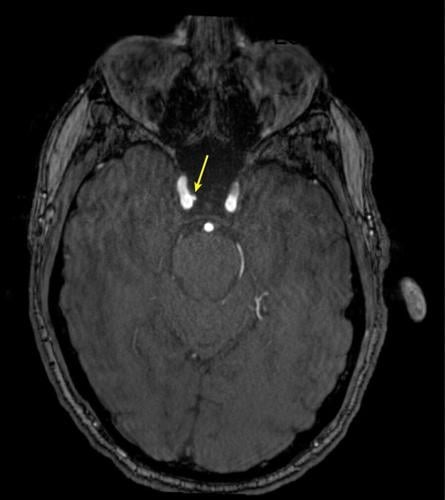

Representative axial time-of-flight MR angiography image in a 35-year-old male participant shows a medially projecting intracranial aneurysm (arrow) originating from the right cavernous segment of the internal carotid artery. (RSNA via SWNS)

De Giorgi said: "Intracranial aneurysms were three times more common in highly exposed personnel.

"Even after accounting for other health factors such as age and blood pressure, the association remained significant.

"These findings suggest that repeated blast exposure may leave a measurable vascular signature in the brain."